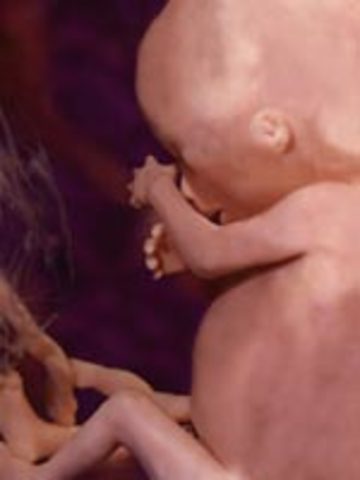

• Week 15: Bones and Muscle growth

Week 15: Bones and Muscle growth

The fetus, which can now be called a baby is 10cm in length and weighs about 2.5 oz. The skin is thin, the body is longer than the head and the arms and legs have grown. The baby's muscles and bones are continuously growing and adult taste buds have developed.

Facts: -The fetal crown to rump length by this week of pregnancy is 4 to 4.5 inches

-The baby's thin skin is covered with ultra fine, downy hair